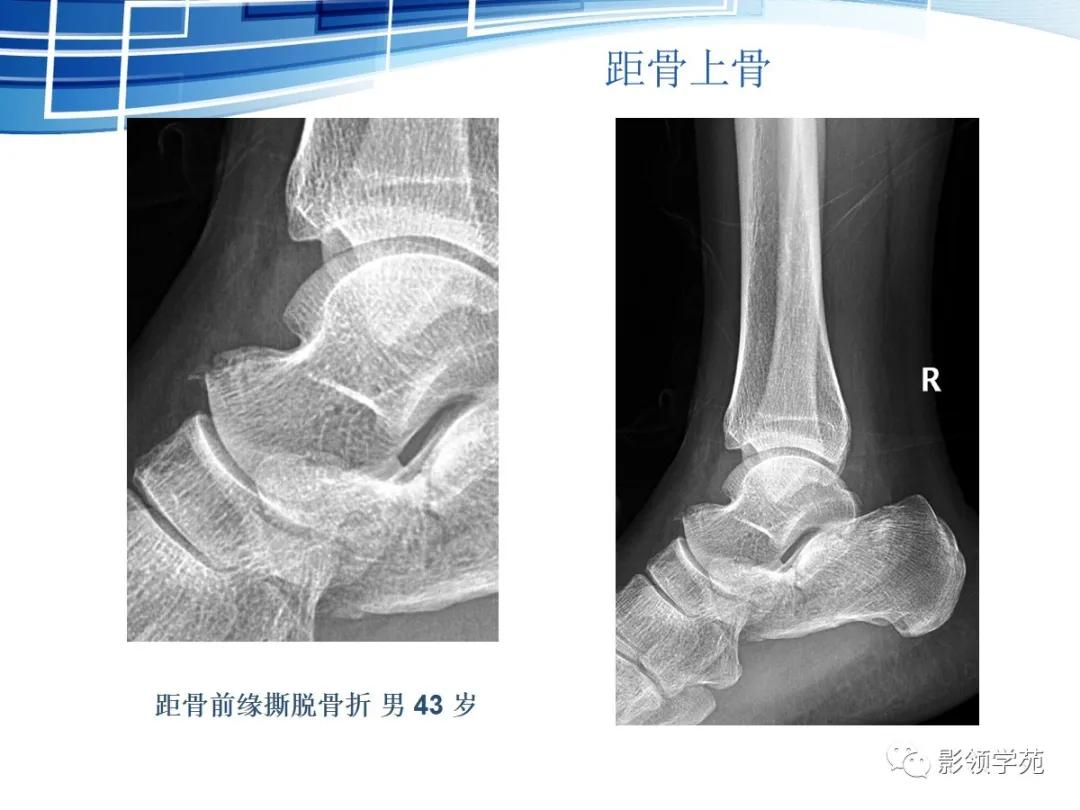

副骨

副骨是由于某一块骨的多个骨化中心在发育过程中没有融合、以致形成多出一块或几块的小骨,也可以是由一个额外的骨化中心发育而来。

撕脱性骨折的影像学特征

具有典型的好发部位,如肱二头肌肌腱附着处撕脱引起的肱骨大结节撕脱骨折。

具有骨折的直接、间接征象,例如撕脱后的游离骨及所对应的受损骨,其骨皮质不连续或缺损,且其边缘锐利、清晰(CT更能清楚显示);MRI可示局部软组织肿胀、积液或积血等改变;最有利的证据是伤后一段时间,上述征象发生了如边缘骨质吸收、有骨硬化、骨痂生长、局部软组织肿胀消退等动态改变。

虽然撕脱性骨折与永存骨骺、籽骨和副骨在影像学上均有游离的小骨块影的表现,但前者具有骨折的影像学一般特征,而后三者不具有。

常见案例均具有骨块边缘钝圆、骨皮质连续、局部软组织无明显肿胀以及伤后该骨的连续摄片无明显变化等非撕脱性骨折的共同特点。

鉴别重点:独立的骨结构(游离骨)若与相对骨的缺损缘相吻合,是撕脱,如有外伤,更支持。

籽骨、副骨与永存骨骺一般边缘光滑, 周围皮质密度较高, 皮质光整, 附近骨质结构完整, 具有对称性, X线随诊形态及位置不会发生改变, 一般不会引起疼痛。但个别患者由于一些局部肌肉的扭伤而引起副骨的移位, 或由于机械外力的作用使副骨摩擦软组织导致滑囊炎和肌腱炎, 甚至由于长期慢性磨损可与附近正常骨质形成假关节从而产生创伤性关节炎可引起疼痛。而骨折一般具有明确的外伤史, 附近软组织肿胀明显, 疼痛症状明显, 断端锐利, 皮质断裂, 不具有对称性, X 线随诊形态及位置可发生移位。而籽骨、副骨与永存骨骺本身也可在外伤的情况下发生骨折, 但极罕见。